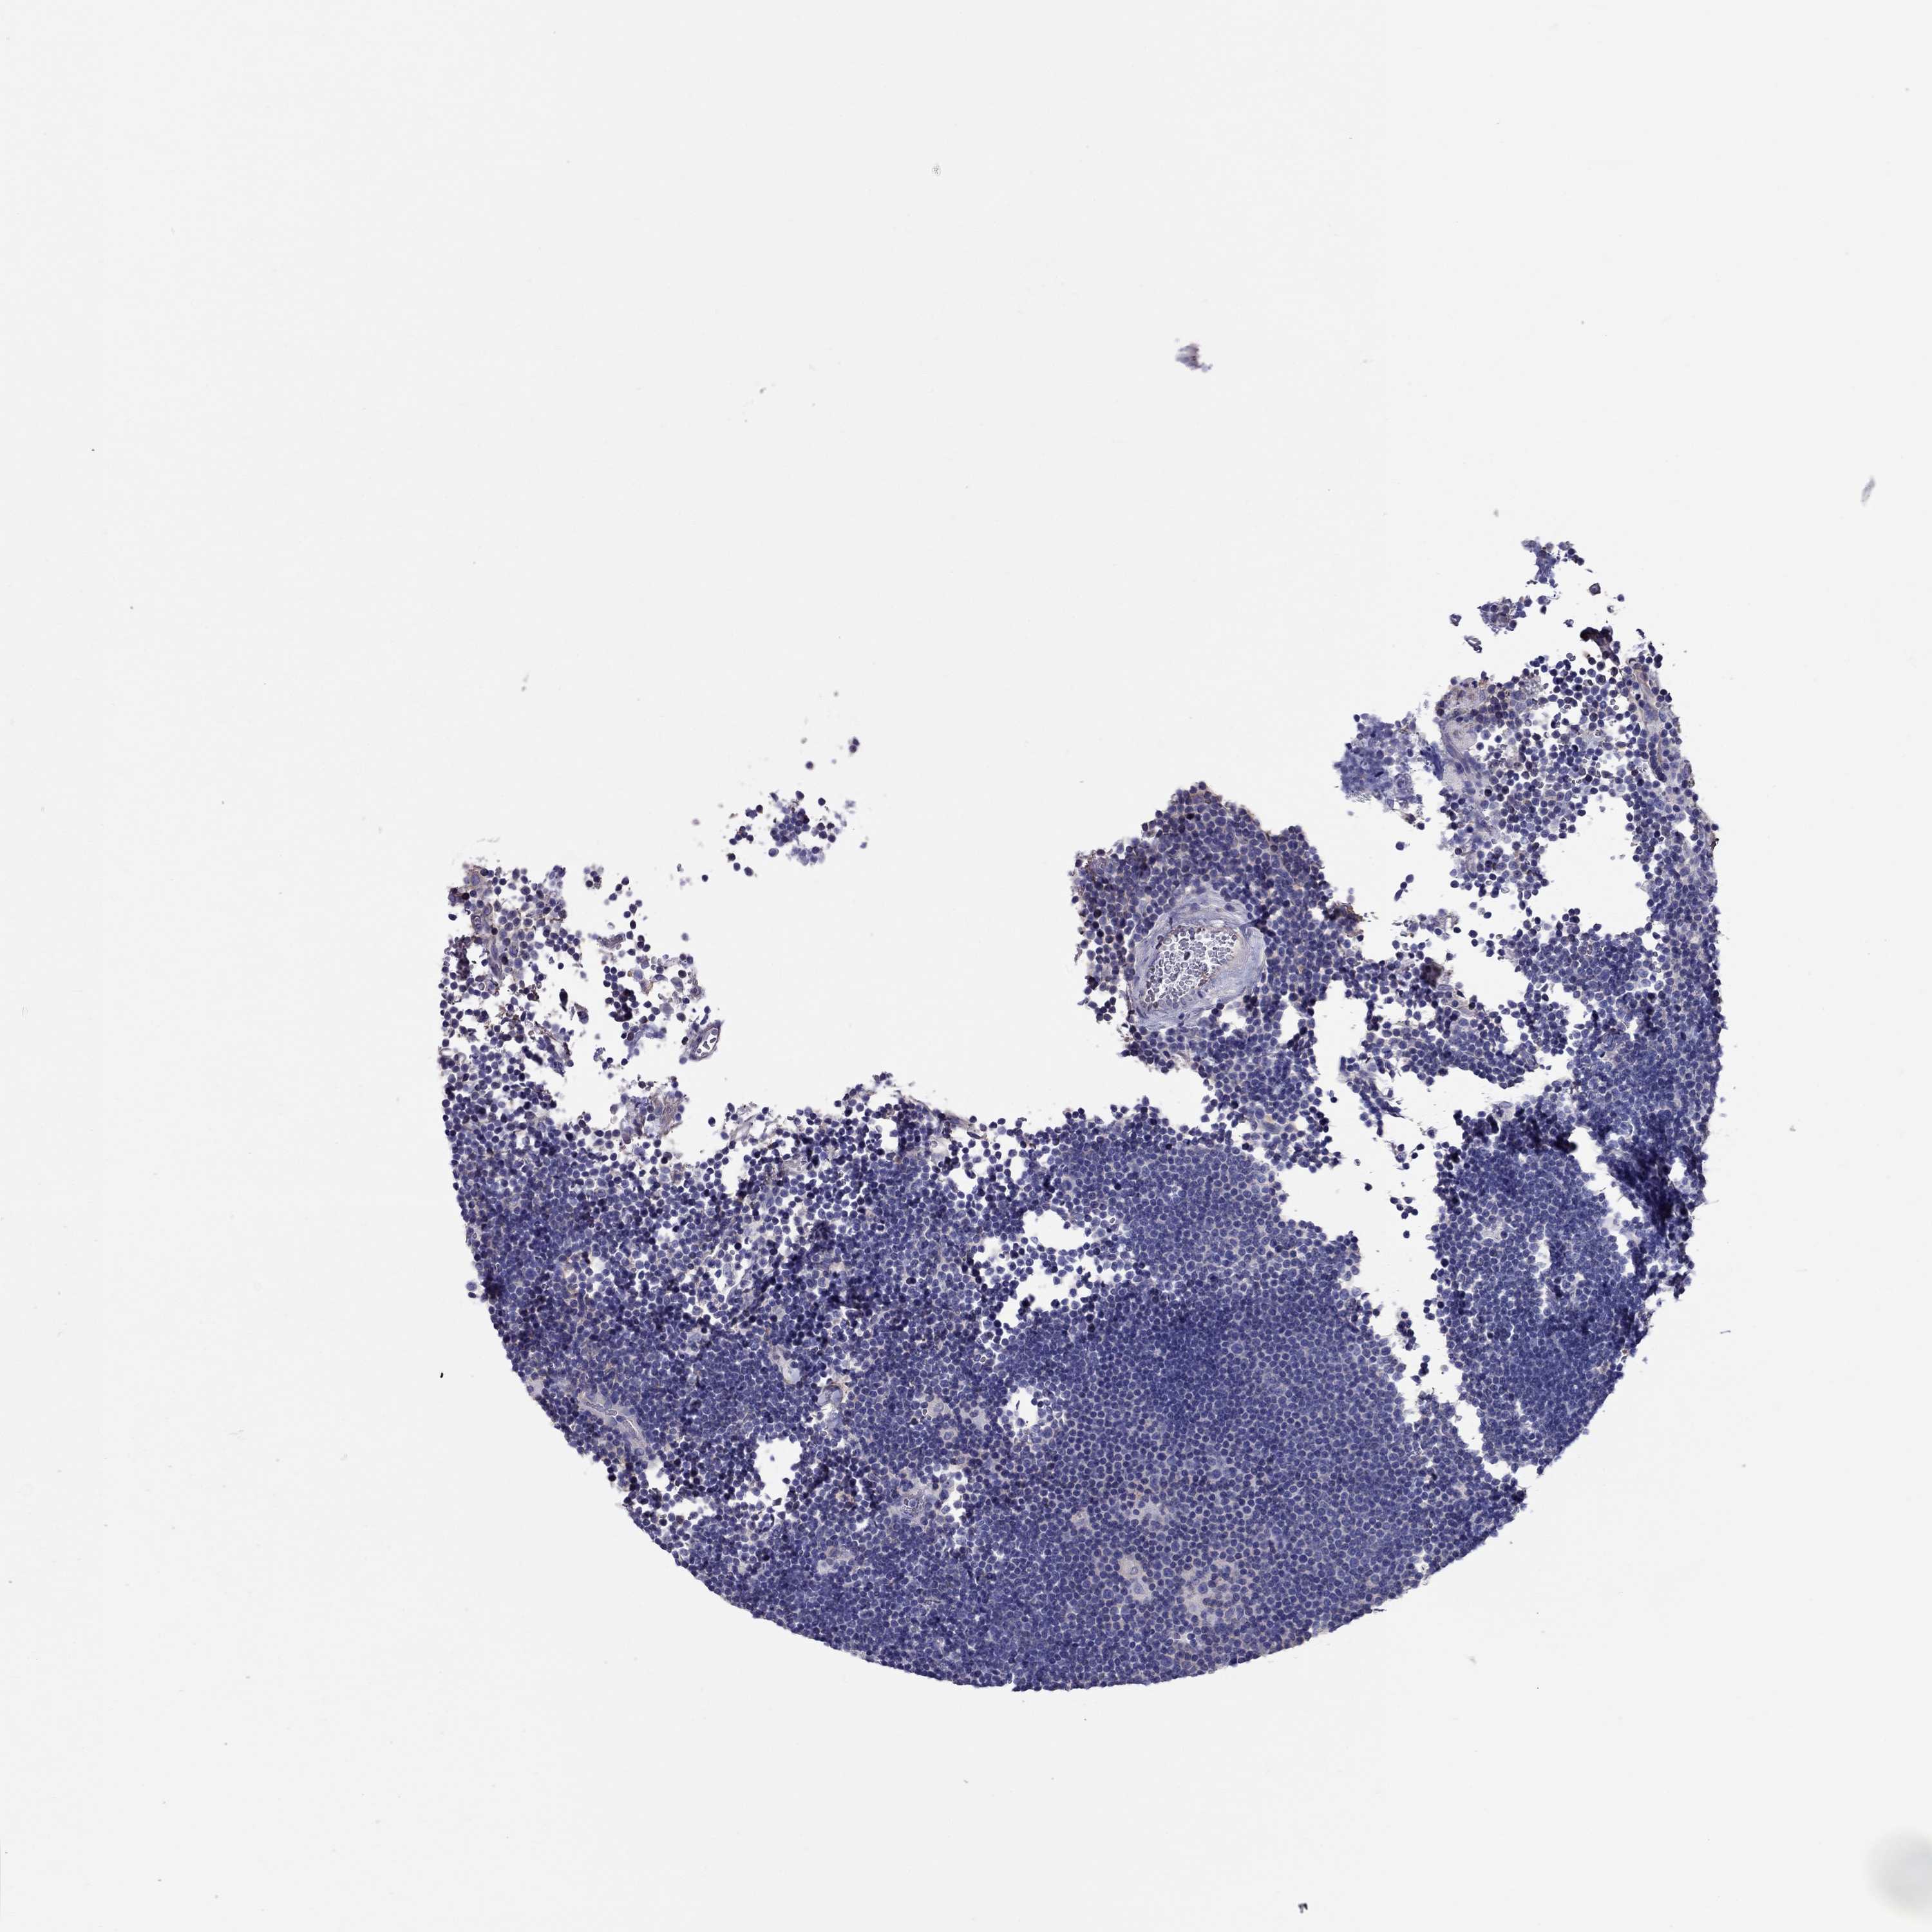

CANCER LYMPHOMA Show tissue menu

LYMPHOMA - Protein expressioni

A mouse-over function shows sample information and annotation data. Click on an image to view it in a full screen mode. Samples can be filtered based on level of antibody staining by selecting one or several of the following categories: high, medium, low and not detected. The assay and annotation is described here.

Each image is clickable and will lead to virtual microscopy that enables deeper exploration of all samples and also displays staining intensity scores, fraction scores and subcellular localization as well as patient and tissue information for each sample.

Antibody HPA065576

Staining

High

Medium

Low

Not detected

Intensity

Strong

Moderate

Weak

Negative

Quantity

>75%

75%-25%

<25%

None

Location

Nuclear

Cytoplasmic/membranous

Cytoplasmic/membranous,nuclear

Malignant lymphoma, non-Hodgkin's type, Low grade

Malignant lymphoma, non-Hodgkin's type, High grade

Hodgkin's disease, NOS